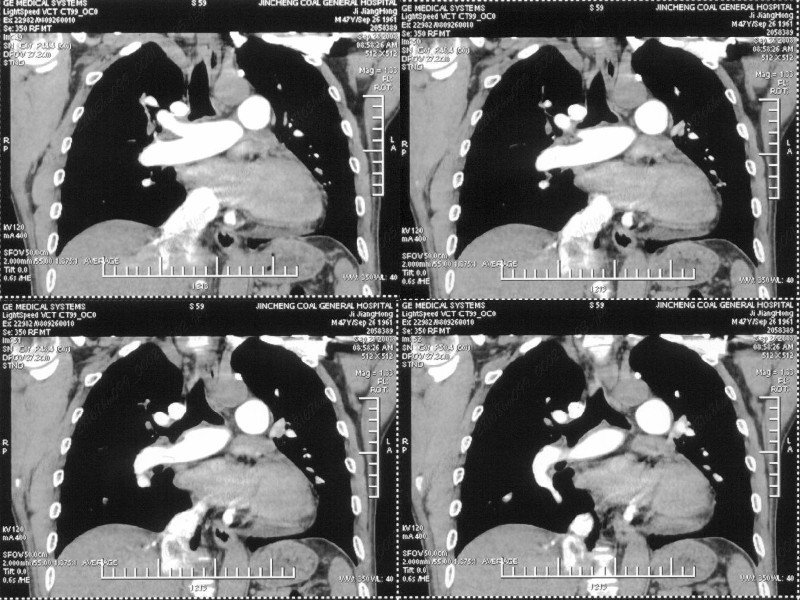

男性,47岁。胸部不适一年,ct检查发现右胸膜下结节。http://www.radida.com/bbs/forum.php?mod=viewthread&tid=46094

右肺中叶外侧段胸膜下结节状病灶,性质待定(不排除周围型肺癌可能)。

汇报临床诊断:右肺动脉分枝栓塞

右肺静脉充盈缺损,左心房体积小,右肺动脉远端动脉充盈缺损,右肺血管影细小,考虑;右肺动脉远端栓塞.

右肺中叶外侧段占位,考虑周围型肺癌伴局限性肺气肿,不除外炎性假瘤